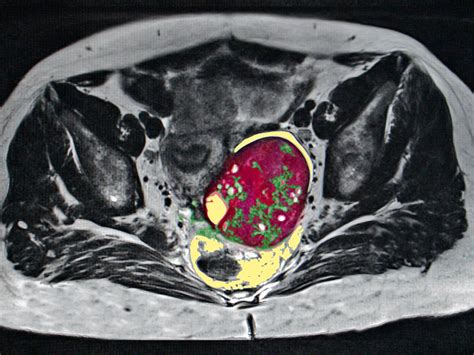

A CT scan uses X-ray technology combined with computer processing to create highly detailed images of your organs, soft tissues, and blood vessels. Unlike a standard X-ray, which produces a flat image, the CT scanner rotates around your body, capturing multiple angles that are then reconstructed into a 3D view. This level of precision is crucial for distinguishing between simple fluid-filled cysts and more complex masses that might require surgical intervention.

• Rule out malignancy: If a cyst appears complex, has solid components, or has irregular walls, the doctor may order a scan to assess for signs of cancer.

Once the scan is complete, a radiologist will interpret the images and send a report to your primary doctor or gynecologist. The results will describe the cyst in detail, often noting its size in centimeters, its composition (whether it is fluid-filled, solid, or mixed), and whether there is any evidence of fluid leakage or involvement of adjacent structures.

After receiving the report, your doctor will discuss the findings with you. Depending on the diagnosis, the approach may range from "watchful waiting"—where the cyst is monitored via follow-up ultrasounds—to hormonal medications or surgical removal. Knowing the specifics provided by your ovarian cyst CT scan allows you and your medical team to make informed, data-driven decisions about your reproductive health.